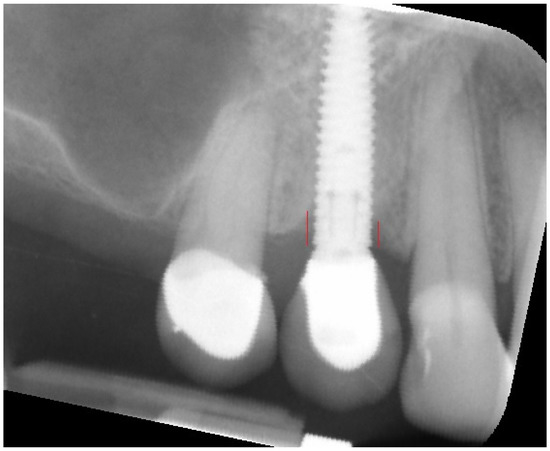

Figure 2.

Measuring of marginal bone loss on the radiographic images. Red lines indicate the implant platform to the bottom of the bone loss cavity.